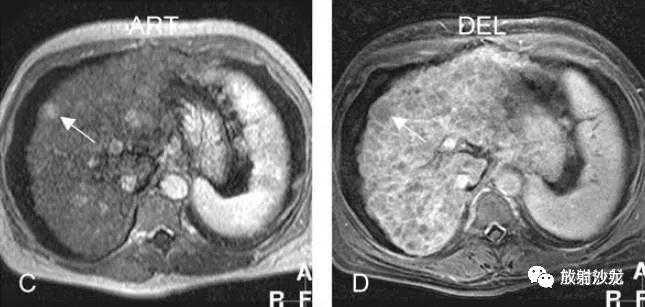

肝硬化,DN,MRI表现:

E:反相位,大部分肝结节呈较高信号;

F:同相位,肝内部分结节因铁沉积呈低信号;脾脏亦可见低信号的Gamna-Gandy小体;

G:动脉期,局部放大图像,大结节强化较明显;

H:延迟期,局部放大图像,大结节并未见肿瘤包膜。